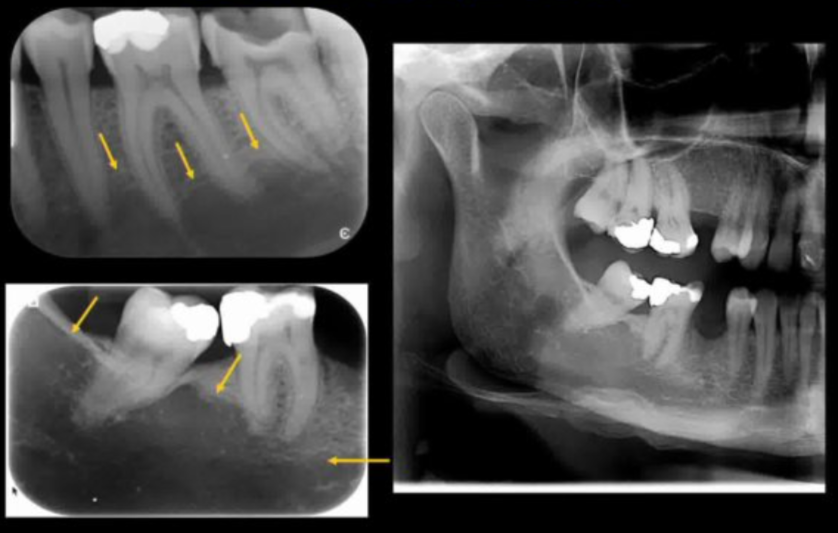

explain the steps in which this periapical periodontitis shown has occured

1) bacterial ingress via caries/ cracks . fractures / marginal gaps in restorations 2) reversible pulpitis ---> irriversible pulpitis ---> pulp necrosis ---> root canal system becomes infected 3) inflamm response happens 'periapical periodontitis' occurs to confine infection/ bacterial ingress 4) the body results in resorption, formation of granulation tissue (cysts may also occur) resulting in radiolucency 5) bone foramtion may also occur - may result in corticated (white) margin and/or general sclerosis of adjacent bone (to wall off infection)